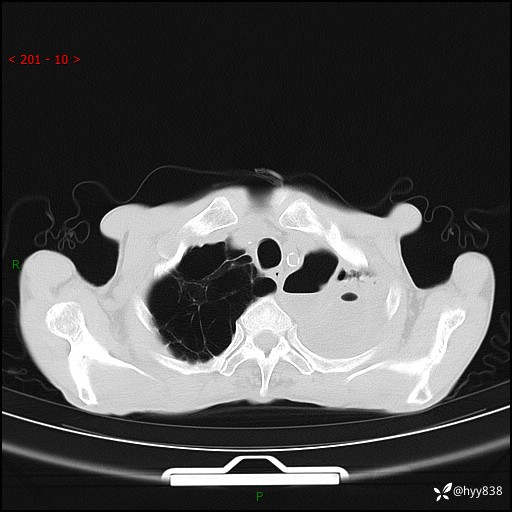

老年男性,反复咳嗽、咳痰、气喘10余年,再发3天。大叶性实变+胸膜病变-结果公布

胸部CT平扫+增强